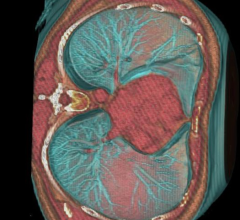

Radiation dose continues to rise as the number of computed tomography (CT), nuclear, angiography and fluoroscopy examinations grow, leading to a greater risk of patient overexposure to radiation. Healthcare providers must reinforce their efforts to monitor and visualize dose levels from radiology examinations to enhance patient safety and meet new regulatory demands. There also is a need to justify and optimize the usage of radiation dose to find a balance between safer practice, image quality and lower dose — all for the benefit of the patient. Implementing tools for automatic and continuous follow up of radiation dose is at the forefront of meeting these challenges.

The advent of hybrid PET/MR in 2011 brought the promise of vastly improved imaging technology in the form of a new modality that combined whole body positron emission tomography (PET) with magnetic resonance (MR) technology. Following two years of using PET/MR, we are seeing clinical benefits with this system at the University Hospitals Seidman Cancer Center in Cleveland.